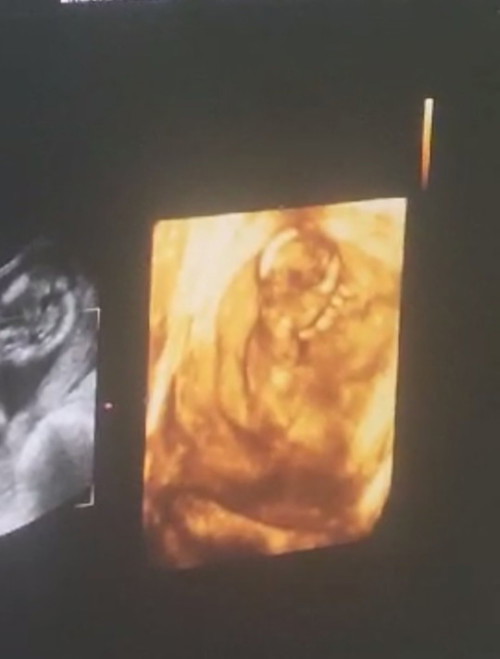

คุณหมอบอกว่าหนูนอนหนุนแขนตัวเองอยู่ค่าาส น่ารักกกก 💕